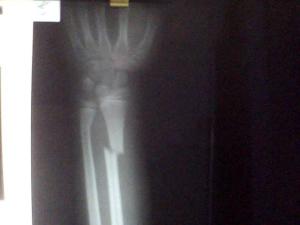

♥桡骨干骨折

桡骨干骨折仅占前臂骨折总数的12%,以青壮年人居多。本病患者伤后前臂出现肿胀、疼痛,可无显著畸形。损伤处有明显压痛,前臂活动明显受限。[1]